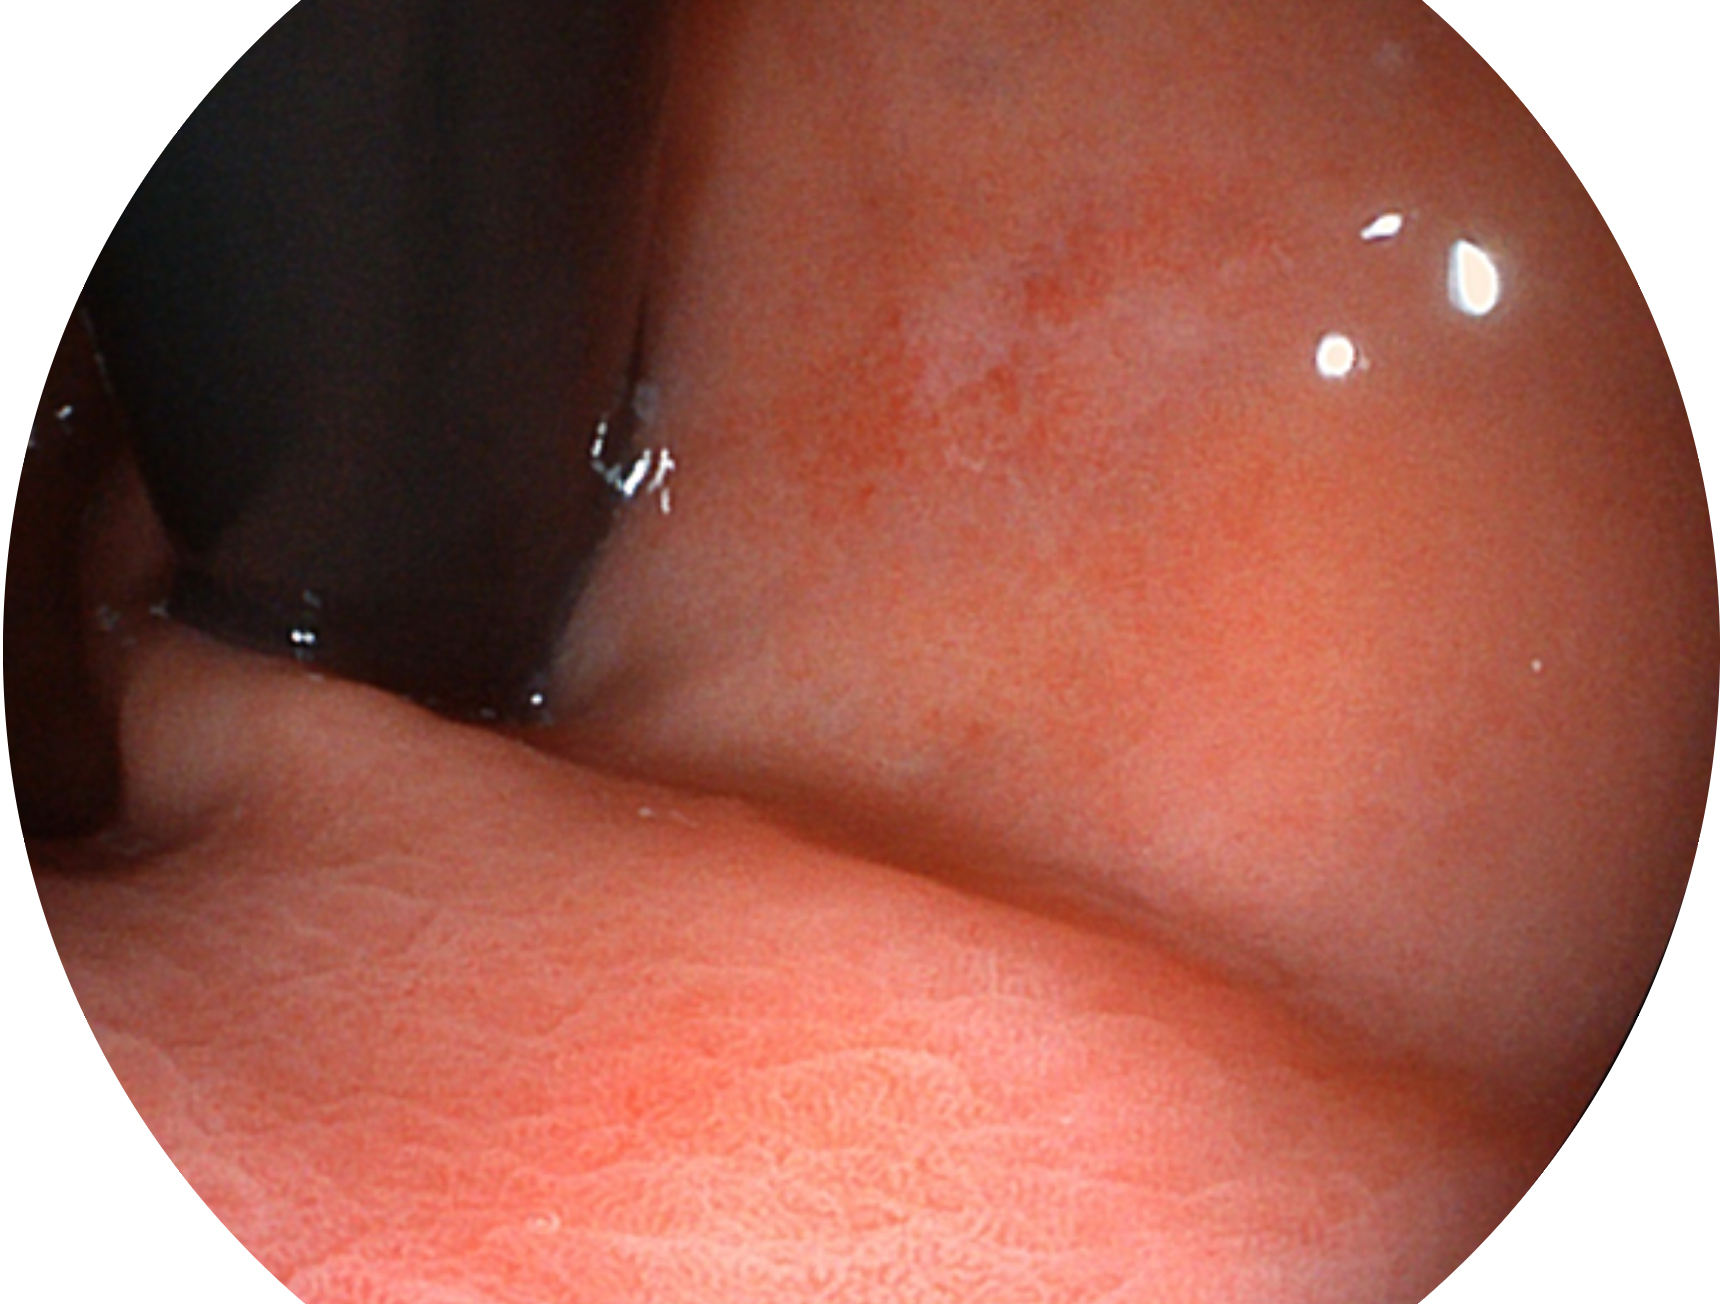

db真人体育官网新开发的内镜染色技术,主要是基于多波长LED 光源的开发,VLS-55Q 四波长LED 光源是由四个不同颜色的LED光按照相应照明模式所规定的特定发光比例进行合束后形成,合束后形成的照明光的光谱由红光、绿光、蓝光及蓝紫光这四个不同的波段范围构成。具有更高光谱自由度,通过光谱比例的控制,实现了聚谱成像技术,英文全称为“Spectral Focused Imaging, SFI”,缩写为“SFI”和光电复合染色成像技术,英文全称为“Versatile Intelligent Staining Technology, VIST”,缩写为“VIST”。